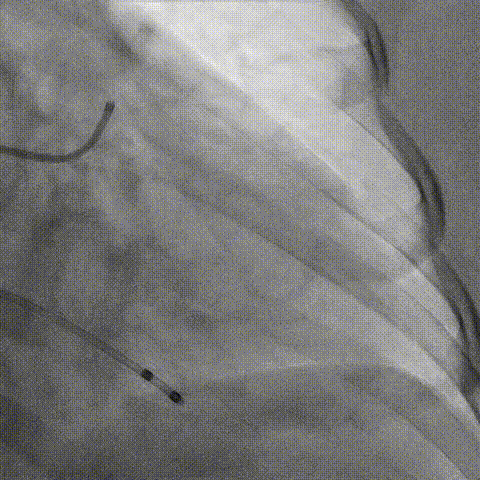

造影评估

支架内后扩张

冠脉造影

根部造影

最终结果